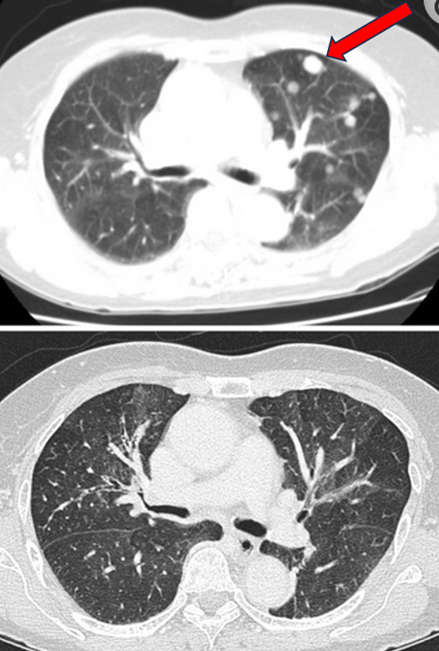

Multiple lung nodules disappeared after high-dose IV vitamin C treatments.

Top: before photo; Bottom: after photo.